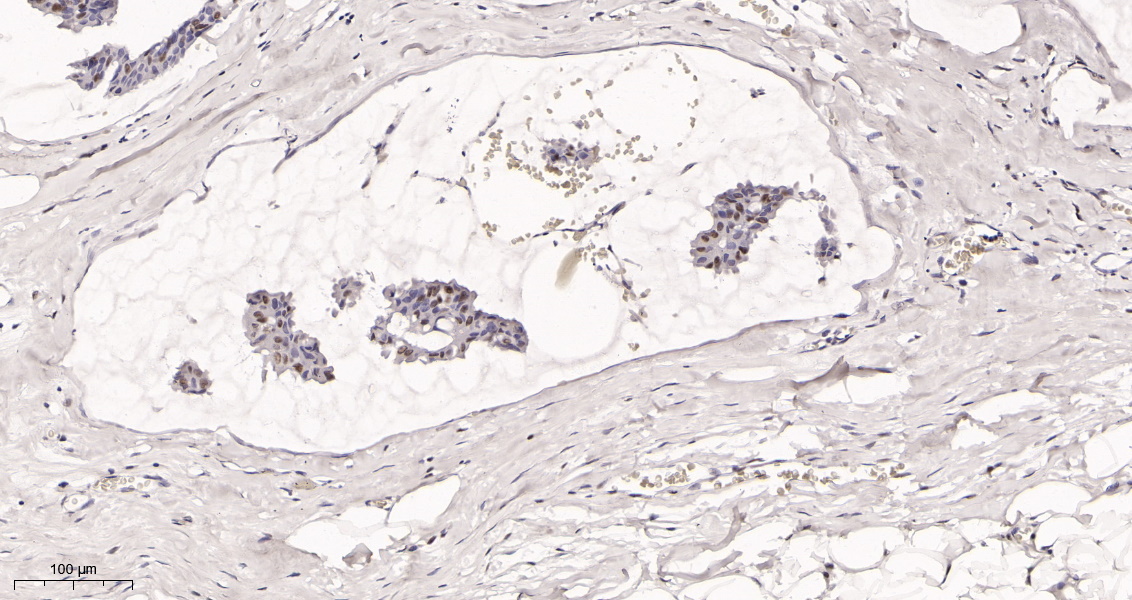

产品名称Rad21 (16H8) Rabbit Monoclonal Antibody

推荐应用WB,IHC-P,IF-P,IF-F,IF-ICC,IP,ELISA

稀释度IHC-P 1:200-1000,WB 1:1000-5000,IF-P/IF-F/IF-ICC 1:200-1000,ELISA 1:5000-20000,IP 1:50-200

背景介绍The protein encoded by this gene is highly similar to the gene product of Schizosaccharomyces pombe rad21, a gene involved in the repair of DNA double-strand breaks, as well as in chromatid cohesion during mitosis. This protein is a nuclear phospho-protein, which becomes hyperphosphorylated in cell cycle M phase. The highly regulated association of this protein with mitotic chromatin specifically at the centromere region suggests its role in sister chromatid cohesion in mitotic cells. [provided by RefSeq, Jul 2008].